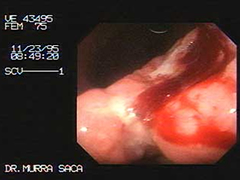

Sangramiento del tubo digestivo superior por carcinoma del fondo:

Paciente fue referido de un colega de la Ciudad de Sonsonate.